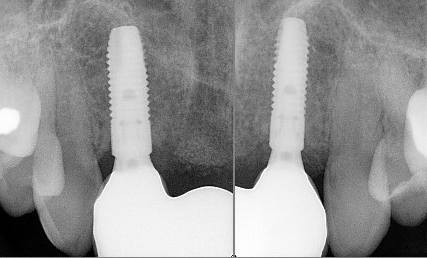

A dental implant is a titanium post that serves as a replacement for the root of a missing tooth. The implant is surgically inserted into the jawbone, where it is fused with the bone as the latter heals over time in a process called osseointegration. Once integrated, the implant becomes a sturdy foundation for one or more artificial teeth.

Dental implants are made up of three key components:

- Implant post: The titanium screw that is placed into the jawbone.

- Abutment: The connector piece that attaches the implant post to the restoration.

- Restoration: The final artificial tooth or teeth, designed to look and function like natural teeth.

Unlike traditional tooth replacement options such as bridges or dentures, dental implants replace the tooth both above and below the gumline, providing superior durability, comfort, and longevity. Implants restore your smile to its natural state, enabling you to eat, speak, and smile with ease.